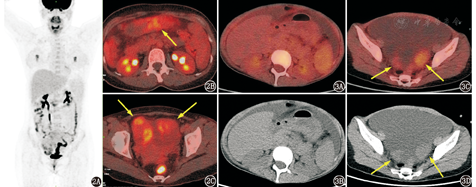

卵巢无性细胞瘤、卵黄囊瘤等生殖细胞来源恶性肿瘤好发年龄为青少年,一般<20岁,与本例流行病学不符。卵巢性索-间质来源肿瘤可为良性或恶性,即便为恶性通常也为低级别,与本例的代谢特点较符合,而卵巢颗粒细胞瘤由于可分泌雌激素或孕激素,常常以相应的内分泌症状起病,包括子宫内膜增生、阴道出血等,本例患者无雌激素相关症状,不支持,因此若考虑性索-间质肿瘤则更有可能为卵泡膜纤维瘤。卵巢转移瘤多发生于胃肠道肿瘤等易发生腹腔种植转移的肿瘤,值得注意的是,当胃肠道肿瘤为代谢活性不高的类型(如胃印戒细胞癌)时,其卵巢的转移灶也可代谢不高或仅轻度升高(图2,图3),同时腹膜、网膜的种植转移灶也可能为假阴性。本例附件区病变代谢不高,伴大量腹盆腔积液,患者为老年女性,因此恶性病变中需高度警惕卵巢转移瘤,在查看图像时需特别关注胃肠道,需判断检查时胃充盈程度如何、胃壁代谢是否均匀、胃壁是否有局部增厚、胃壁有无可疑的僵硬等表现,另外还需仔细观察腹膜、大网膜是否有结节、絮状影、局部增厚等隐匿性种植转移的表现。本例胃肠道未见异常,也未发现隐匿性的种植病灶,临床上血清CA125高而CEA正常,暂无支持性证据,若有胃镜检查结果则可更有把握地排除这一诊断。肉瘤的代谢程度变异较大,取决于具体的病理类型,脂肪肉瘤等恶性程度较低的肉瘤可以仅有轻中度代谢增高,而像横纹肌肉瘤等恶性程度较高的肉瘤代谢常明显增高,本例附件区占位代谢轻中度增高,若考虑肉瘤则可能为低级别的类型。